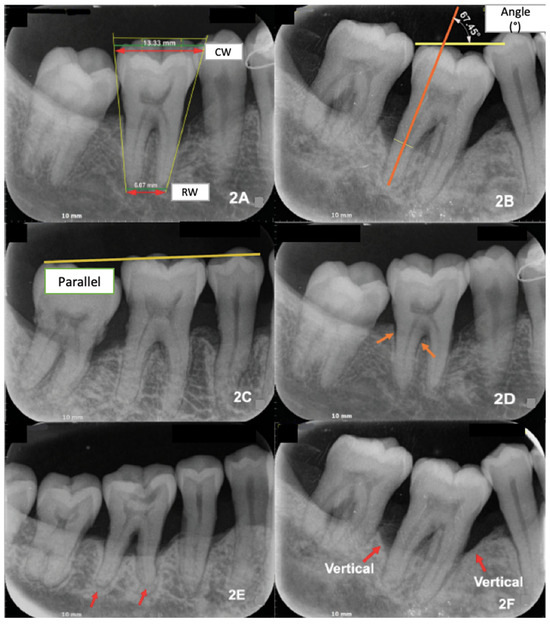

2.3. Operational Definitions and Measurements